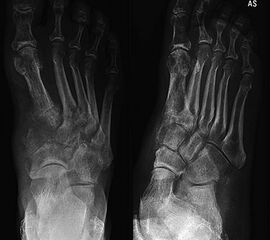

Das solitäre Enchondrom ist von Enchondromatosen, also disseminierten Enchondromen der Extremitäten und des Achsskeletts, abzugrenzen. Die Entartungswahrscheinlichkeit ist für Enchondromatosen wie dem M. Ollier (Abb. 18a und b) oder dem Maffuci-Syndrom deutlich erhöht und wird in der Literatur bis zu 25% angegeben. Klinische und radiologische Hinwiese für eine Entartung beinhalten Kortikalisveränderungen, wie -verdickung, -destruktion und die enossale Kortikalisarrosion, welche in der CT-Bildgebung mehr als 2/3 der Zirkumferenz des betroffenen (Röhren-) Knochens umfasst.